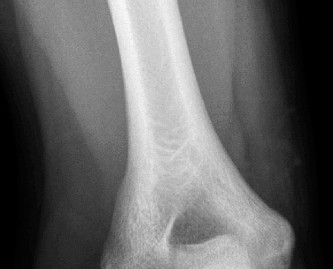

The correct answer is (E). Given that her rotator cuff has atrophied and has fatty infiltration to the point where there are equal parts fat and muscle, this is considered an irreparable rotator cuff tear. Repair should not be attempted because of poor outcomes following repair (see last two paragraphs of this discussion below). A reverse total shoulder arthroplasty is an alternative to repair that should be used in cases of massive, irreparable rotator cuff tears. It is a semi-constrained prosthesis that restores function in patients with massive rotator cuff tears by constraining a concave humeral cap inferior to a semispherical glenoid component (glenosphere). This creates an inferior force-couple and a fulcrum that replaces the stabilizing function of the infraspinatus maintaining a center of rotation around which the shoulder can move. This allows the deltoid to abduct and flex the shoulder without causing the humerus to migrate superiorly and about the acromion. In an elderly patient with a massive, irreparable rotator cuff tear (as in this patient), a reverse total shoulder arthroplasty is the procedure of choice.

It should be noted that reverse total shoulder arthroplasty is also the procedure of choice in patients with cuff-tear arthropathy (aka rotator cuff arthropathy). Characteristics of cuff-tear arthropathy include superior migration of the humerus due to a massive rotator cuff tear, glenohumeral joint destruction, subchondral osteoporosis, and humeral head collapse (see Fig. 2–17). A reverse total shoulder

arthroplasty in this case serves the purpose of eliminating pain caused by glenohumeral joint arthritis while restoring functional motion and is the procedure of choice in patients with cuff-tear arthropathy.

Figure 2–17_X-rays of a patient showing evidence of cuff tear arthropathy. The humerus is migrated superiorly, the glenohumeral joint is destroyed, there is subchondral osteoporosis, and the humeral head is collapsed. (From Ecklund KJ, Lee TQ, Tibone J, Gupta R. Rotator cuff tear arthropathy. _J Am Acad Orthop Surg. 2007;15(6):340–349.)